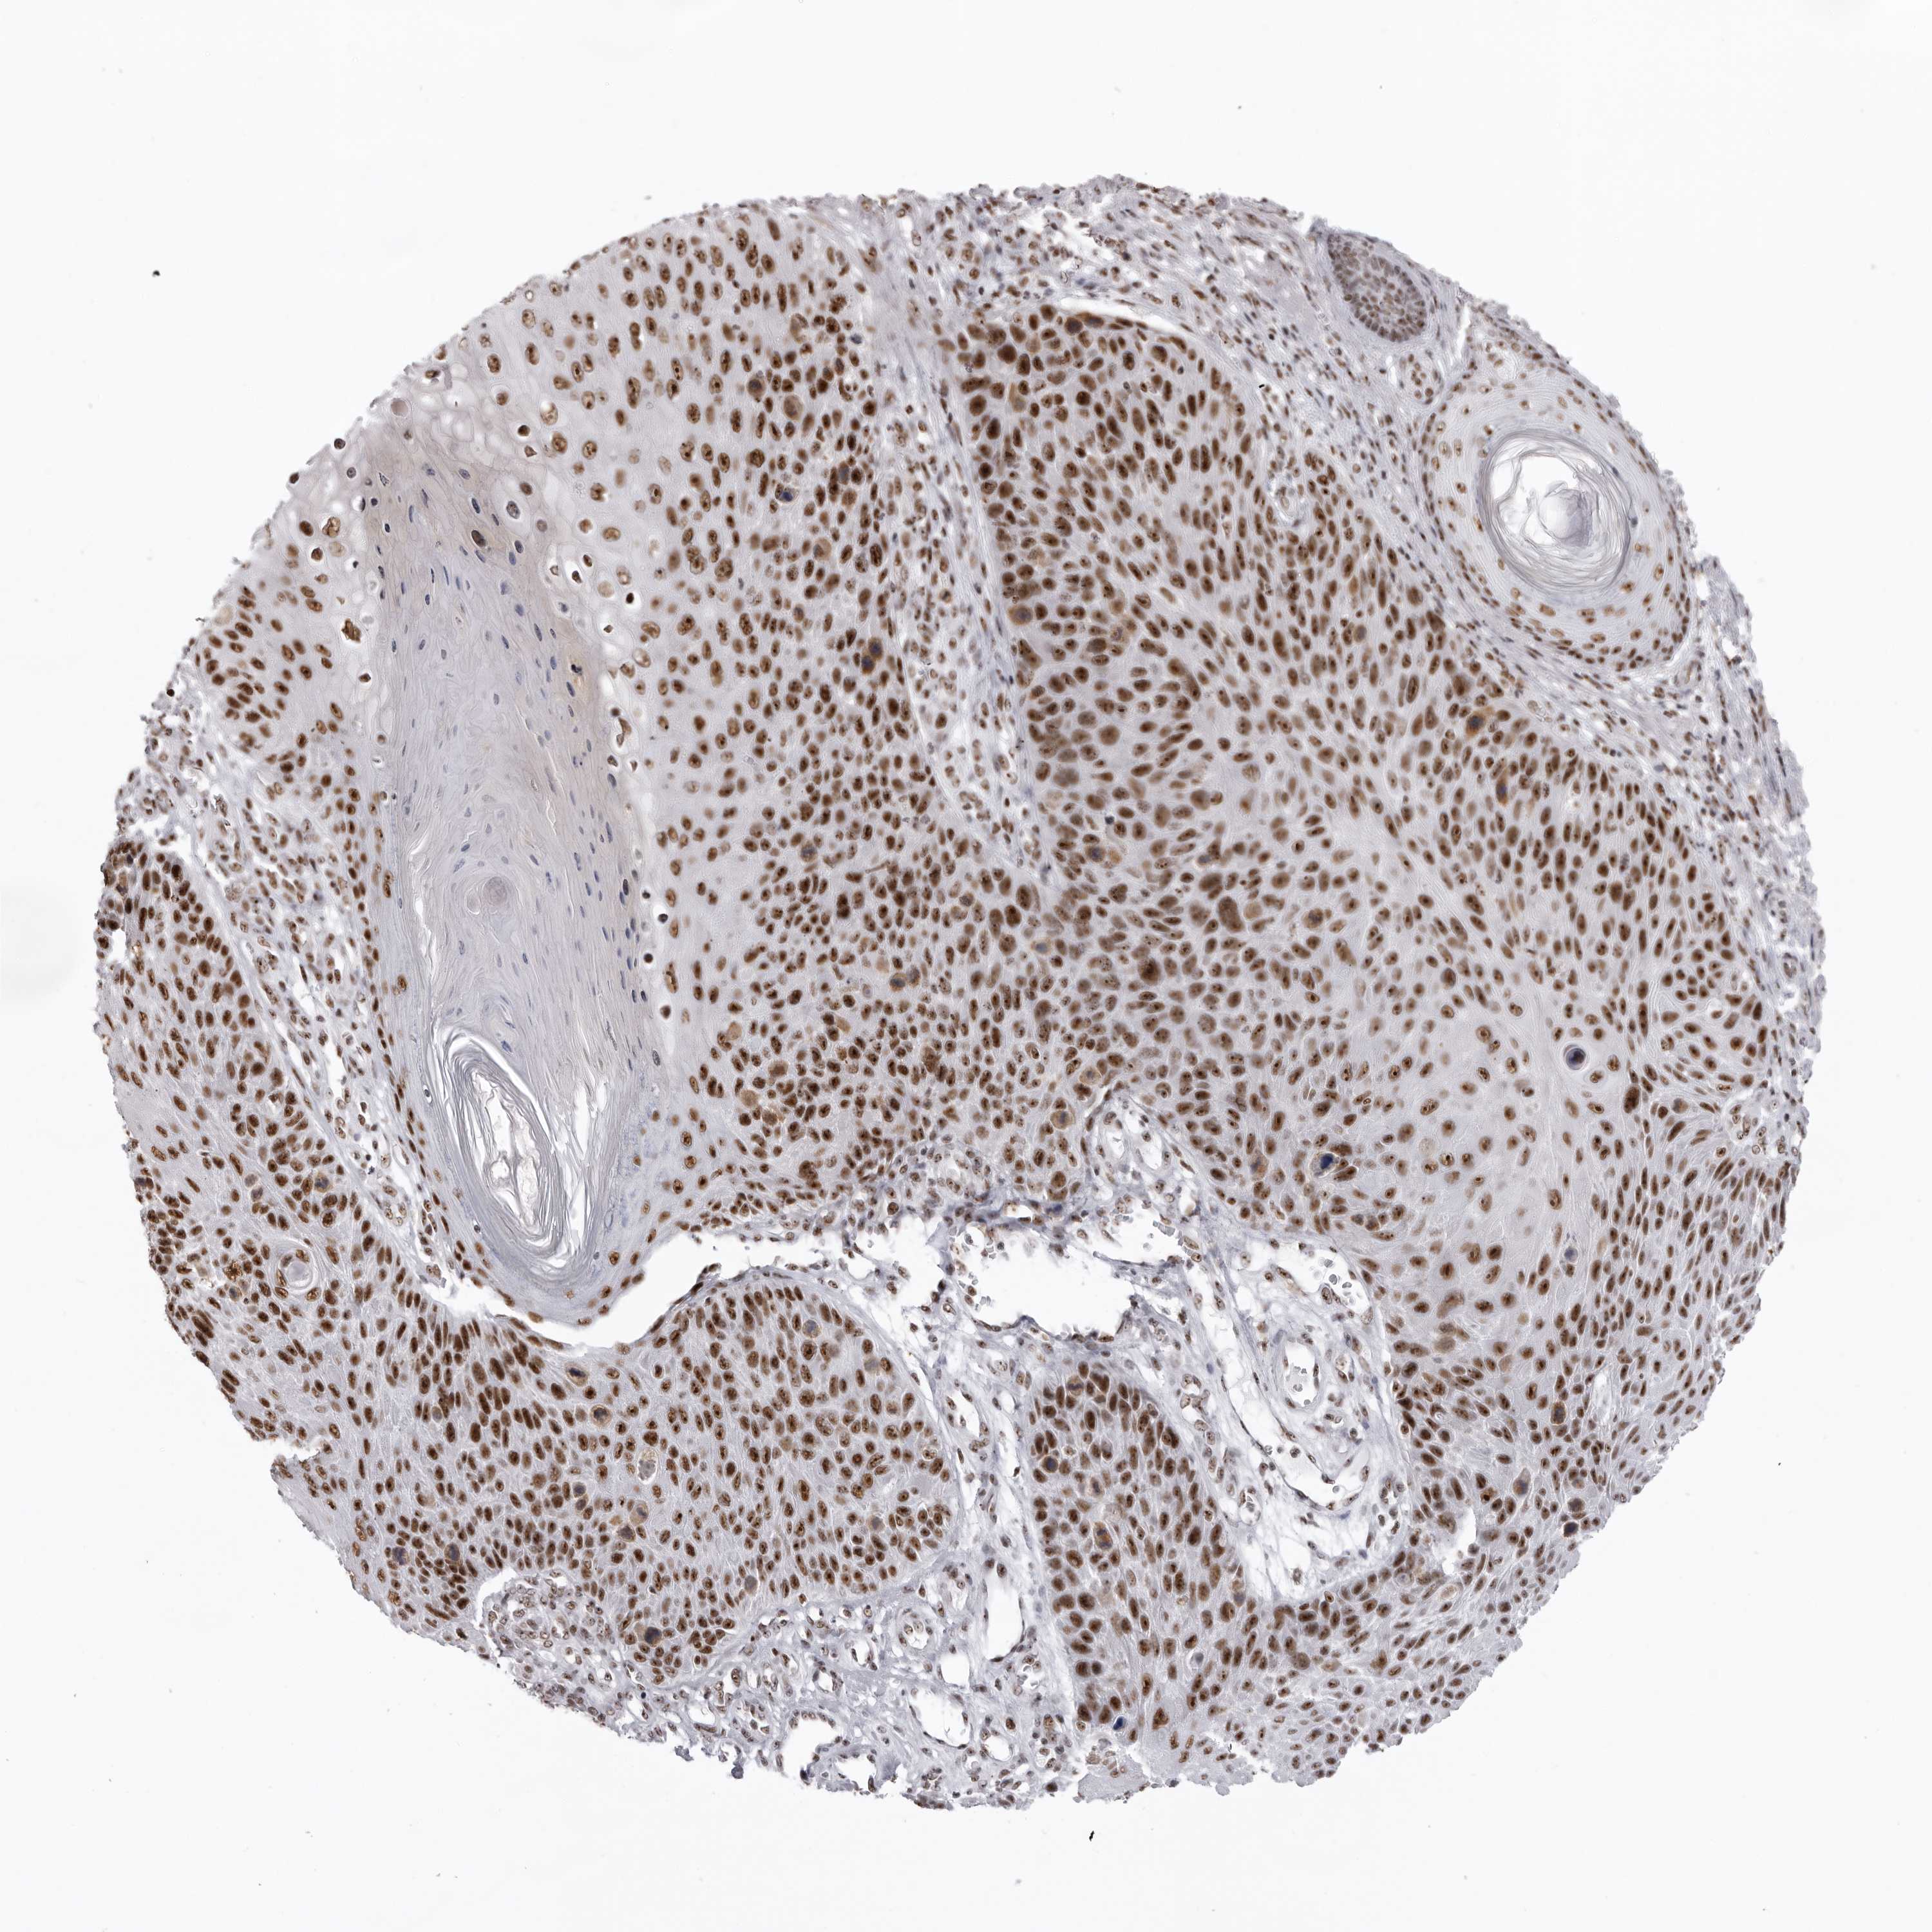

SKIN CANCER - Protein expressioni

A mouse-over function shows sample information and annotation data. Click on an image to view it in a full screen mode. Samples can be filtered based on level of antibody staining by selecting one or several of the following categories: high, medium, low and not detected. The assay and annotation is described here.

Each image is clickable and will lead to virtual microscopy that enables deeper exploration of all samples and also displays staining intensity scores, fraction scores and subcellular localization as well as patient and tissue information for each sample.

Antibody HPA028050

High

Intensity

Strong

Quantity

>75%

Location

Nuclear

Basal cell carcinoma